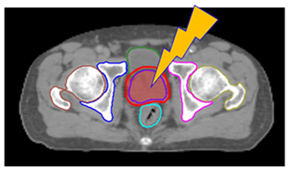

首先設計個人化之固定模具結合個人化腹部壓縮設備,進行4D電腦斷層攝影,必要時結合呼吸調控技術,進行治療前模擬。之後,將各式影像例如磁振照影、電腦斷層攝影與正子攝影等多種影像透過影像融合技術 ,精準定位出腫瘤位置 (圖二),同時醫師透過腫瘤靶區的圈選與透過人工智慧(Artificial Intelligence, AI)系統進行周遭正常組織之標定,與醫學物理師討論進行治療計畫設計,透過動態弧形技術給予腫瘤需的劑量、正常組織須限制的劑量,治療入射角度,治療入射方向等細節,來增加腫瘤精準治療包覆性與成功降低周遭正常組織劑量,來成功達到腫瘤消融與保護正常組織的目的。(圖三)

圖三、與醫學物理師討論進行治療計畫設計,包括腫瘤需給予的劑量、正常組織須限制的劑量,治療入射角度,治療入射方向等細節,來增加腫瘤精準治療包覆性與成功降低周遭正常組織劑量